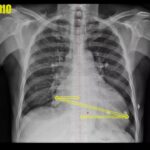

Antes de tudo, é importante destacar que a parte ventricular é a mais importante do músculo cardíaco, pois permite que o sangue saia do coração. Os ventrículos são divididos em direito e esquerdo. O ventrículo direito exerce uma pressão mais baixa em relação ao esquerdo, já que a finalidade dele é enviar sangue para os pulmões. Já o ventrículo esquerdo é responsável por enviar sangue para o corpo inteiro e, por isso, precisa fazer mais força e ter mais pressão para cumprir essa função.

É crucial entender que se houver uma insuficiência ventricular direita, já pode haver prejuízos no corpo do paciente, como acúmulo de sangue na rede venosa e possibilidade de edema, mas o pulmão pode estar normal. Por outro lado, se houver uma insuficiência ventricular esquerda, a casa caiu! O corpo inteiro sofre prejuízos, já que o ventrículo esquerdo manda sangue para todo o corpo e, se ele não está injetando todo o sangue necessário, pode haver retenção de volume e dificuldades na perfusão de oxigênio. Além disso, o átrio esquerdo pode acumular sangue das veias pulmonares, o que pode levar a problemas pulmonares graves.